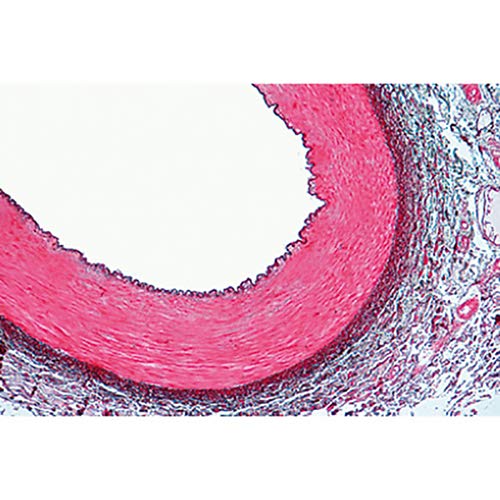

Microscope Slides: 1(d). Trachea, cat, t.s. 2(e). Lung, human t.s. 3(c). Blood, human, Wright stained smear 4(c). Artery, human, t.s., elastica stained